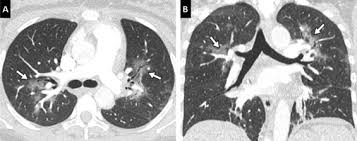

Comment Je Fais Un Scanner Simple Energie Pour Embolie Pulmonaire Aigue Epa

Comment Je Fais Un Scanner Simple Energie Pour Embolie Pulmonaire Aigue Epa from www.elsevier.com

Une irm thoracique sans injection (figure 4) effectuée à titre complémentaire a mis en évidence cette même masse paravertébrale bilatérale hétérogène la myélofibrose pouvait aussi être discutée du fait de la haute densité osseuse au scanner, mais il n'y avait aucun argument biologique en ce sens. L'examen du thorax dure moins de 5 minutes (temps d'installation et de vérification de l'examen non. Le scanner est l'examen de base. Survient dans 18% des traumatismes de la rate. Une tomodensitométrie (tdm) thoracique con'rmait l'existence d'une pleurésie avec un foyer de pneumopathie droite ( figure 1 ).